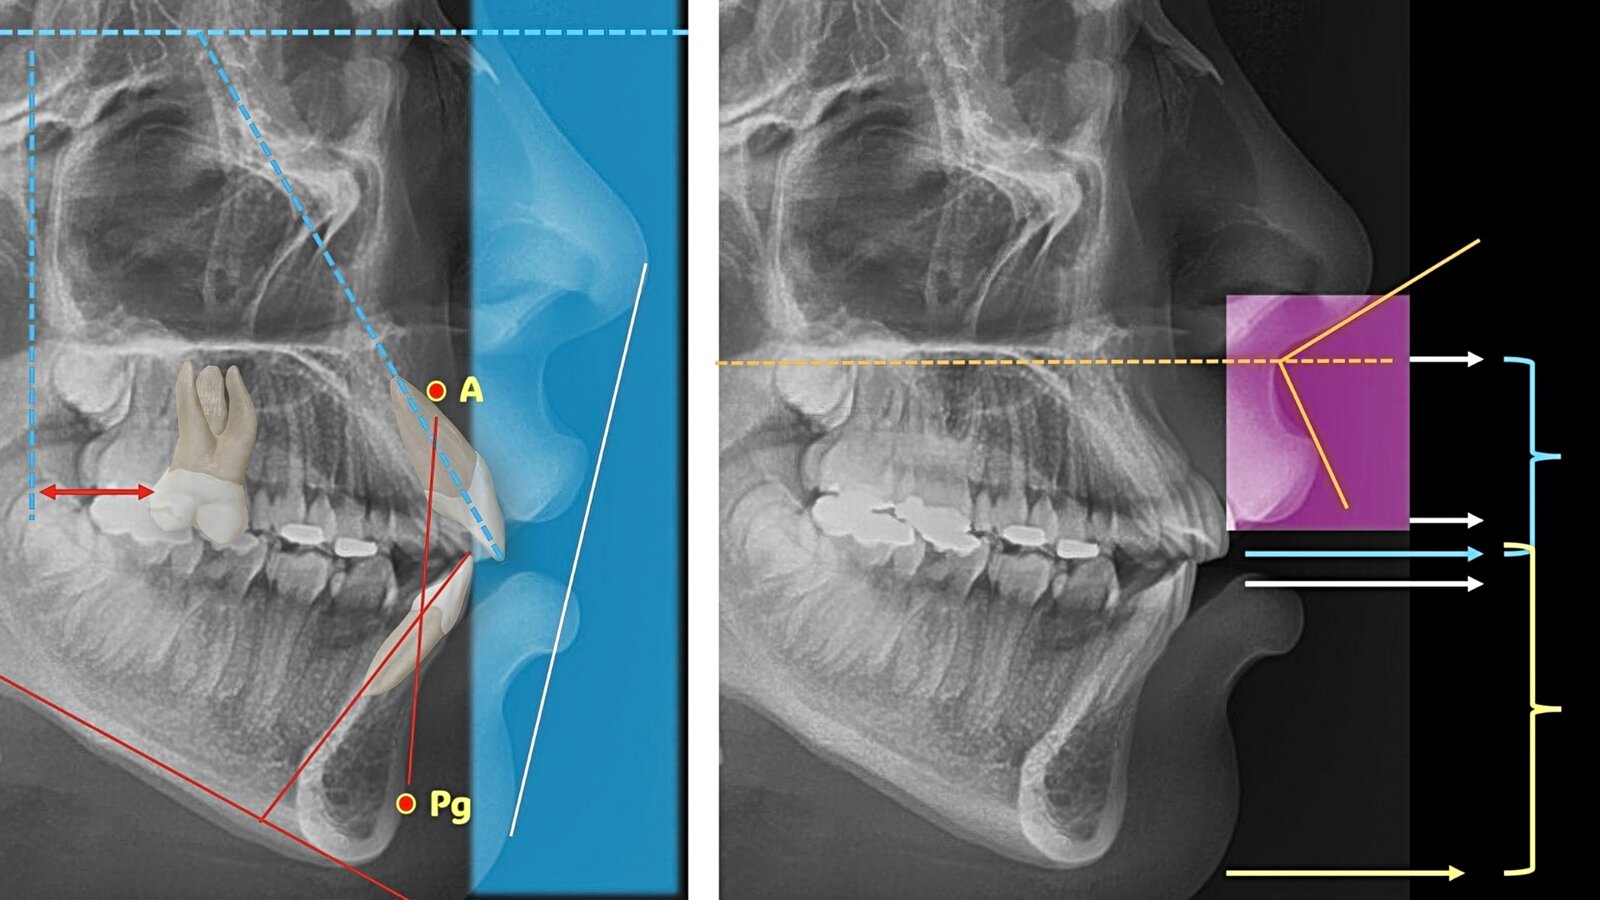

Figura 6. Todos los padres quieren saber cómo será la cara de sus hijos, por lo que la cefalometría tiene enormes capacidades para la venta de tratamientos. Foto: Fotos: Servicio de Investigación en Ortodoncia de la Universidad de Santiago de Compostela.

• Otro elemento poco valorado en la cefalometría clásica es la asintomática rotación de la mandíbula alrededor de su eje de bisagra terminal (EBT), que produce cambios en el ANB a expensas del aumento de la dimensión vertical (por esta posterorotación lenta y asintomática). Así, cuando se nos presenta una gran diferencia entre la relación sagital del ANB (por ejemplo, de Clase II) y la absoluta de ambas longitudes maxilares (Clase I), la medida clave es el Wits Appraisal de Jacobson (dos perpendiculares al plano oclusal funcional desde el punto A y B). Nada más simple, sencillo y eficiente.

• Si bien las cosas no son tan simples como parecerían para soportar las ideas de RM Ricketts, hay un runrún de fondo interesante, que el genial ortodoncista ya supo intuir. Me refiero a la geometría fractal, tan de moda en la comprensión y diseño del cuerpo humano, su relación con los números irracionales, la secuencia anteriormente referida y el antropocentrismo del universo. Ya en ese maravilloso y fructífero siglo IV a.C. griego, Pitágoras afirmaba que el mundo y la filosofía se reducían a geometrizar y entender lo que la naturaleza nos quería decir a través de los números; la mejor aprensión de nuestro mundo, al menos la más exacta, se hace a través de las matemáticas. Una medida muy simple, una increíble expresión no solo de la evolución humana, sino de la capacidad del hueso alveolar para mantener la homeostasis oclusal, un encaje de dientes eficiente, que funcione, consiste en comparar el plano oclusal funcional con la bisectriz formada por la prolongación distal del plano maxilar y mandibular. El crecimiento gnómico, proporcional, de algunas partes de nuestra cara, como la Altura Facial Inferior o el Eje facial son grandes aportaciones de RM Ricketts a nuestra especialidad.